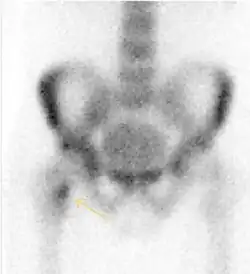

Radiological signs of transient osteoporosis of the hip include localized osteoporosis of the femoral head and neck (Figure 8). Nevertheless, final diagnosis has to be made with MRI to differentiate it from avascular necrosis and from insufficiency or stress fractures of the femoral head or neck. In case of AVN, radiographs can only demonstrate delayed or advanced signs. Staging according to Ficat classification ranges between normal appearance (stage I), slight increased density in the femoral head (stage II), subchondral collapse of the femoral head with or without “crescent” sign (stage III), and advanced collapse with secondary osteoarthritis (stage IV). In the case of stress or insufficiency fractures X-ray sensitivity has been proven to be much lower than MRI, which is currently the gold standard.[1]

Figure 8:

-

X-ray of a patient with transient osteoporosis of the left hip showing osteoporosis.[1] -

Coronal stir imaging in transient osteoporosis, showing diffuse edema.[1] -

Scintigraphy (A), sagittal T1 (B), and coronal PD fat sat of a patient with a subchondral fracture of the femoral head with convex shape to the articular surface.[1] -

Coronal T1 of a patient with avascular necrosis of the femoral head.[1]

Nuclear Medicine

Bone scanning in people with hip pain can be complementary to other imaging studies, mainly in indeterminate bone lesions to clarify whether it is an active lesion with abnormal radiotracer accumulation. Nevertheless, MRI has replaced scintigraphy in the diagnosis of most of these conditions. An example is stress or insufficiency fractures: increased uptake is usually present in around 80% of fractures within 24 h, and 95% of fractures reveal activity by 72 h following trauma, showing an overall sensitivity of 93% and specificity of 95%. MRI is superior to bone scans in terms of sensitivity (99%-100%) and specificity (100%). Moreover, a bone scan does not provide detailed anatomical location of the fracture, and further imaging is usually required.[1]